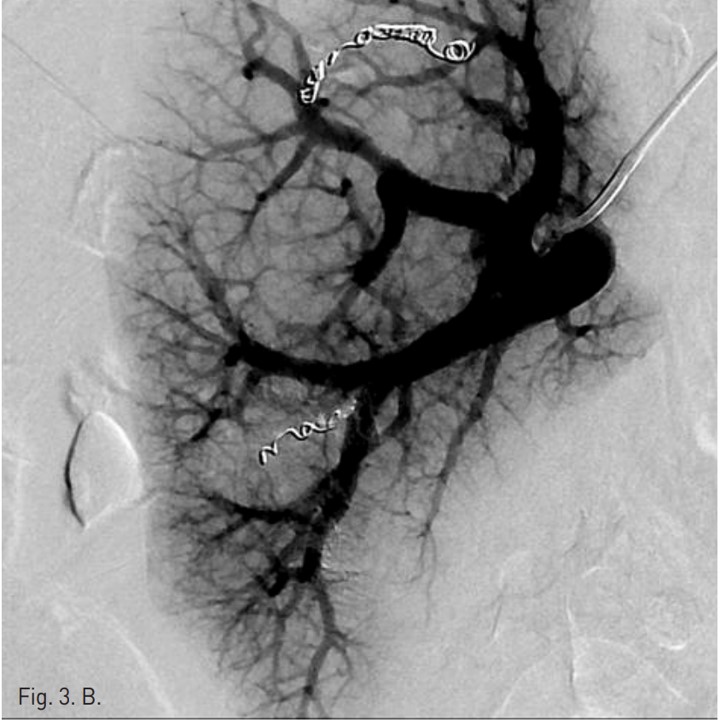

간동맥 혈관 조영을 하기 위해 오른쪽 대퇴동맥 주변을 국소 마취 후, angiocath로 대퇴동맥을 puncture하고 guidewire유도 하에 RH catheter삽입 후 celiac trunk를 선택하여 간동맥 혈관조영을 시행하였다. 간동맥 혈관 조영상에서 분명한 출혈은 보이지 않았지만, right anterior superior hepatic artery에서 arteriovenous shunt가 있어 microcatheter(Sirabe 2.2 Fr)로 간동맥을 선택하여 microcoil (TORNADO microcoil, 4 mm x 2mm, 3 mm x2 mm and 5 mm x 2 mm)과 gelfoam을 이용하여 색전술을 시행하였으나(Fig. 2) 색전술 4시간 후 수축기 혈압이 60 mmHg로 감소되었다. 간동맥 색전술에도 불구하고 계속적인 출혈이 있어서 간문맥 출혈을 의심하였음. Chiba needle로 좌측 간문맥을 puncture하고 guide wire유도 하에 angiography catheter를 삽입하여 간문맥 혈관 조영술을 시행하였다. 간문맥 혈관 조영에서 right anterior inferior portal branch에서 출혈이 관찰되어 microcatheter(Sirabe 2.2 Fr)로 right anterior inferior portal branch를 선택하여 두 개의 microcoil (Nester 35 mm x 4 mm and Tornado 5 mm x 2mm), Glue(Histoacryl 0.5ml) 그리고 Gelfoam을 이용하여 색전술을 시행하였다 (Fig. 3).

Fig. 3. B

B. The right anterior inferior portal branch was embolized with 2 microcoils, glue and gelfoam. After embolization, there was no further contrast extravasation.